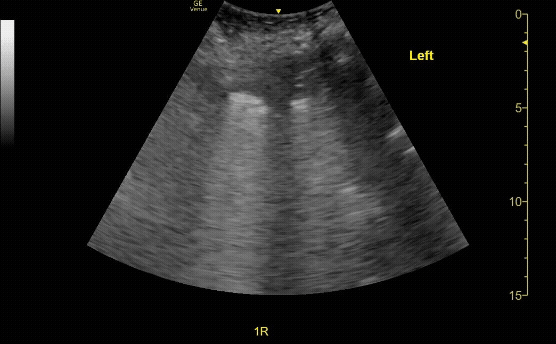

Evaluate the pleural line in both lungs showing lung slide (seen here).

c/o Victoria Gonzalez, MD